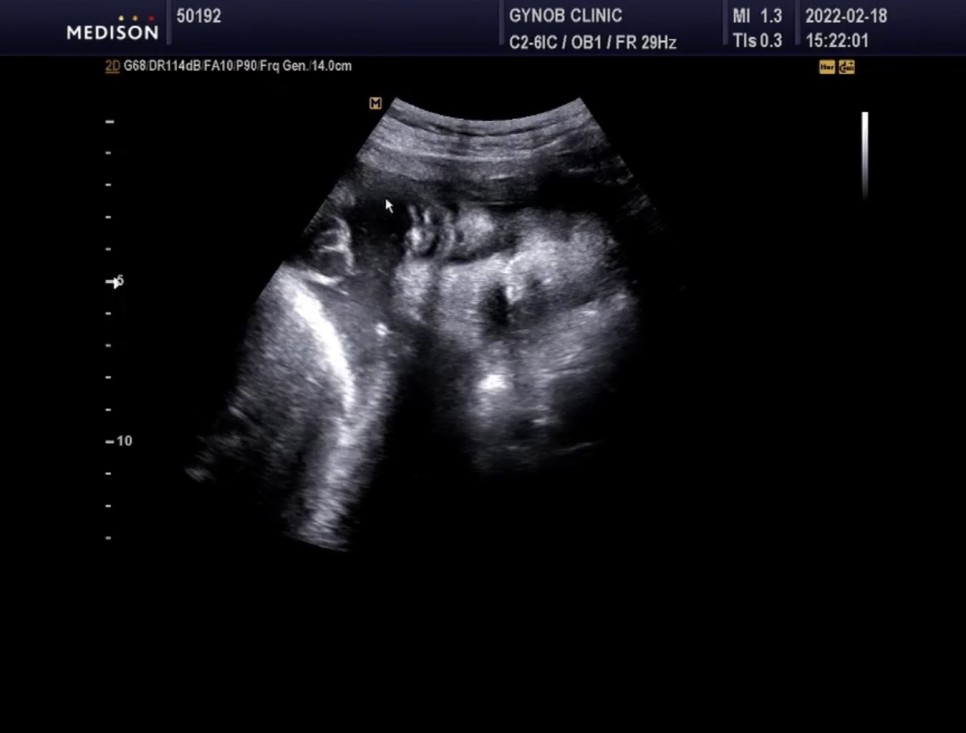

▲초음파실에서 초음파도 봤다=심상덕 원장님은 초음파를 5분 동안 꼬박꼬박 챙겨보신다.

아기의 머리 위치는 정상*경부 제대륜 1회 신경 쓸 필요는 없습니다.

- 경부 탯줄은 탯줄이 아기의 목 부분을 감고 있다는 것을 의미한다

경부제 대륜 1번 탯줄에 목을 1번 감고 있다는 뜻이다.너무 신경 안 써도 될 것 같아

느긋한 얼굴 ㅋㅋㅋ 귀여워 ❤️